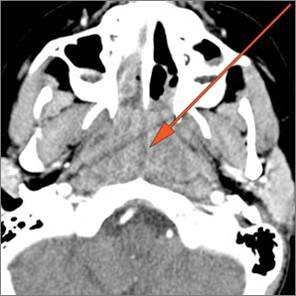

There is edema within the fat of the adjacent retropharyngeal space.

There is an abscess within the fat of the adjacent retropharyngeal space.

There is reactive retropharyngeal lymphadenopathy.

There is suppurative retropharyngeal lymphadenopathy.

If there is suppurative retropharyngeal adenopathy what is the maximum short axis dimension of the largest suppurative node. Measurement

There is edema/abscess within the adjacent parapharyngeal and retropharyngeal spaces.